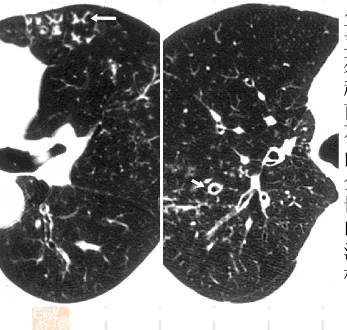

尤文肉瘤:右肺下叶后段结节沿肺动脉周边分布形成树芽征

弥散性泛支气管炎CT图像